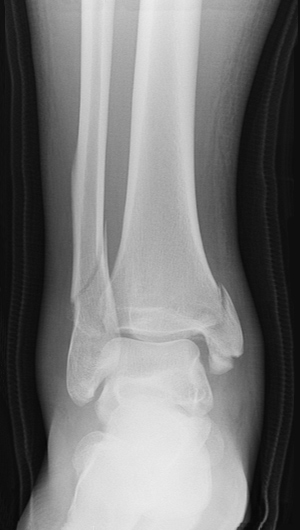

happens in ankle fracture/dislocation

separation of tibia and fibula from talus

ankle fracture / dislocation mechanism (2)

foot forced inward/outward, foot planted and lower leg forcibly rotated

signs/symptoms of ankle fracture/dislocation

severe pain/deformity, open fracture, no weight bearing

ankle fracture/dislocation treatment

immobilize, apply light pressure, ice + elevate if no open wound